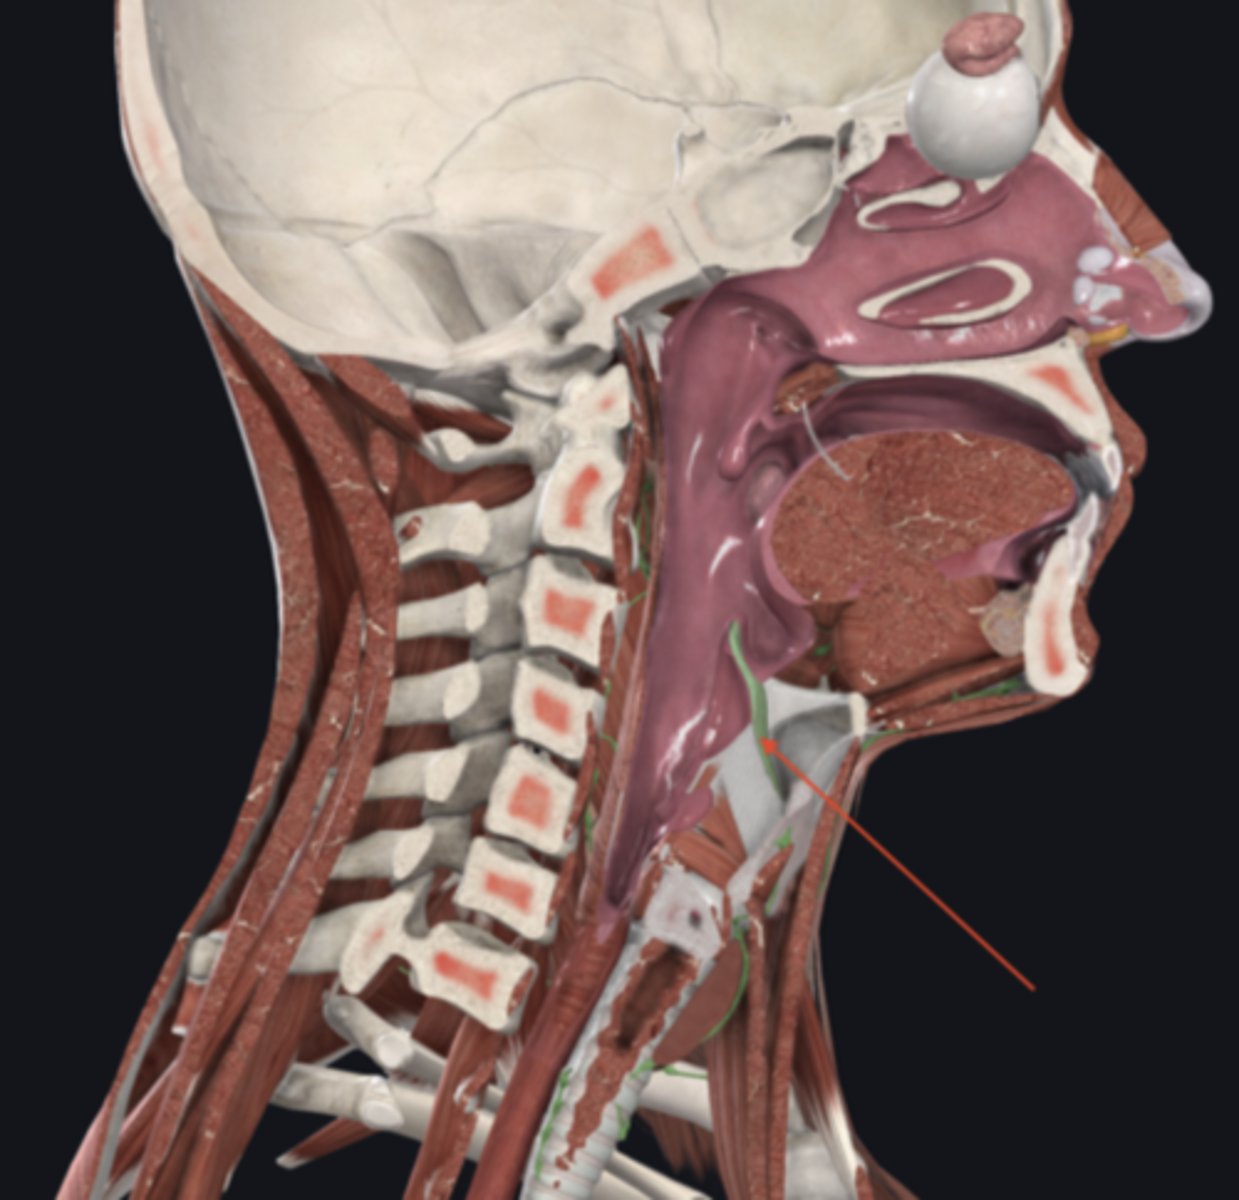

nasopharynx

name the circled region

oropharynx

name the circled region

laryngopharynx

name the circled region

epiglottis

esophagus

upper esophageal sphincter